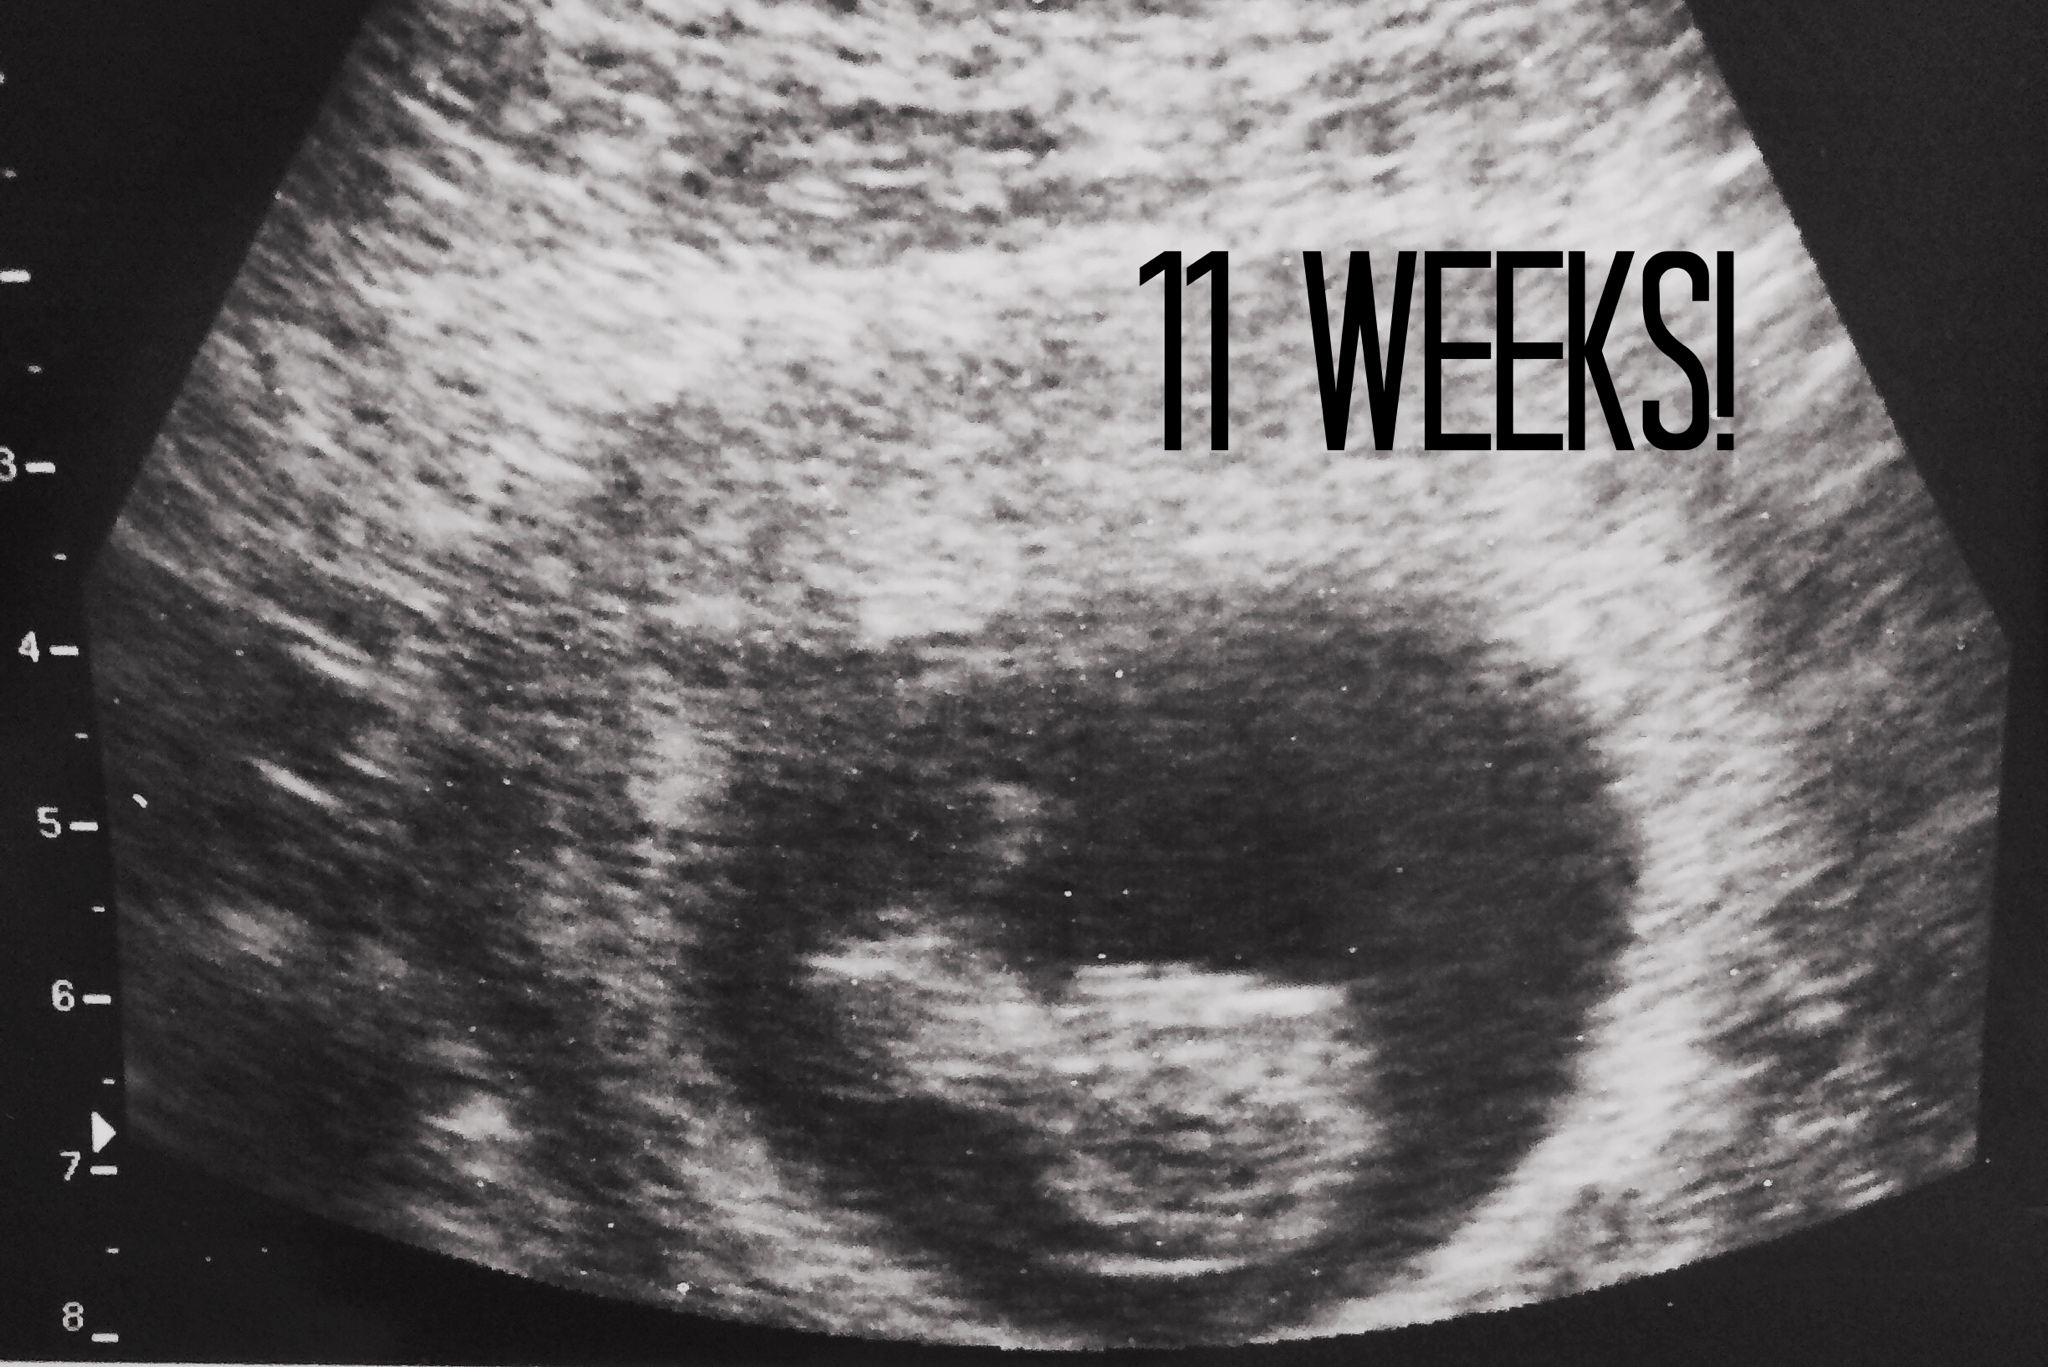

The doctor was very nice; He showed us our little peanut and right away I felt that this little bundle of joy growing inside me was going to be a baby boy! Of course, we shared our exciting news with our families and close friends as soon as we walked out of the doctor´s office.

During one of my appointments, week 12 to me more specific, we had the NT (nuchal translucency scan); one of the most important ones because we were going to be able to find out the percentage of fluid in the back of our baby´s neck. We used to see 2 specialists; the doctor that performed my ultrasounds and my OB/Gyn.